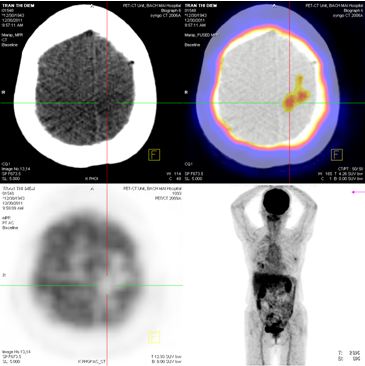

Chụp PET/CT:

Hình 5: Hình ảnh PET/CT có tổn thương cung sau xương sườn số 5 bên trái, và khối u não vùng đỉnh trái

Trước điều trị: tổn thương thùy đỉnh trái 2 cm

Sau điều trị 6 tháng: tổn thương tan hoàn toàn

Hình 8: Hình ảnh PET/CT toàn thân sau 6 tháng điều trị: Khối u não vùng đỉnh trái tan hoàn toàn.

Trước điều trị: Tổn thương cung sau xương sườn số 5 bên trái

Hình 9: Hình ảnh chụp MRI sọ não sau 6 tháng xạ phẫu bằng dao gamma quay: Khối u não di căn vùng đỉnh trái tan hoàn toàn